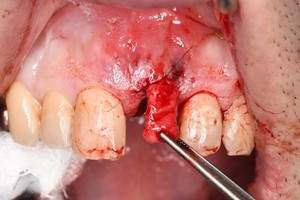

症例写真-2

- Befor

- 途中経過

- After

| 年齢 | 50代・男性 |

| 主訴 | 右下歯が疼く |

| 治療内容 | ・右下6番インプラント ※1:FGG(遊離歯肉移植術)とは、足りない歯ぐきを上顎から上皮を切り取り移植する外科手術 |

| 治療費 | 合計:902,000円(税込) ■内訳 |

| 治療期間 | 9ヵ月 |

| 治療方針 | 右下の当該歯は歯根破折により保存不可能と診断しました。歯周疾患も伴っていたため抜歯後に骨吸収※1が大きく起こることが予測できました。チタンメッシュ併用骨再生誘導法(GBR※2)を選択しインプラント埋入と同時に行い自然な歯槽骨のラインを再現しました。またGBRを行う際にインプラント辺縁の付着歯肉の減少が起こる為、遊離歯肉移植術(FGG※3)を行い清掃性を考慮した形態に仕上げました。 ■治療方針の解説 治療した右下の歯をレントゲンで撮影したところ根本の部分に黒く写る箇所があり「根尖性慢性周囲炎※1」と診断。また歯周病も進行していました。 ※1 骨吸収・・・歯槽骨という歯を支える骨がなくなっていくこと |

| 担当者所見 | 主訴の右下だけでなく歯茎の腫れ、発赤があり不良補綴や不良充填など他にも治療箇所が多数ありました。プラークコントロールが不良であった為まずはブラッシング指導を行いセルフケアの重要性を理解していただくところからスタートしました。 右下6番の歯はインプラント治療を行なった結果審美的にも機能的にも患者様の満足を得ることができました。骨造成と歯肉移植も行なった為インプラントを支える十分な歯周組織の獲得ができたと思っております。 |